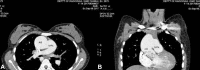

Figure 10

Cardiac CT (transverse and coronal section) showed origin of aorta from right ventricle and origin of main pulmonary artery from aorta through aortopulmonary window.